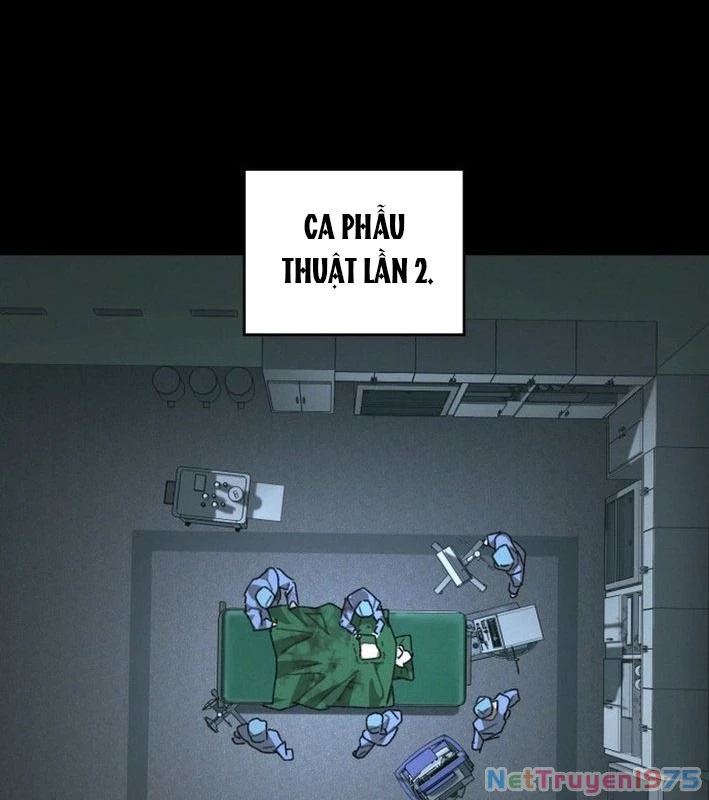

Kẻ Chôn Cất Quái Vật - Chapter 1